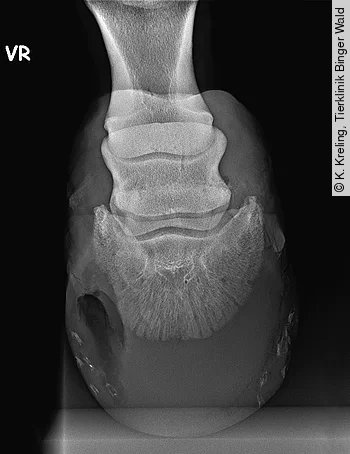

Die Gefahr von nicht vollständig ausgeheilten Hufabszessen liegt vor allem darin, zu Hornsäulen mit chronischen Lahmheiten möglicherweise mit Beteiligung der knöchernen Strukturen (genauer: des Hufbeins) und der Entstehung einer Osteomyelitis zu führen (Abb. 3). Ein Hufabszess darf deshalb nicht unterschätzt oder gar als Bagatelle abgetan werden.